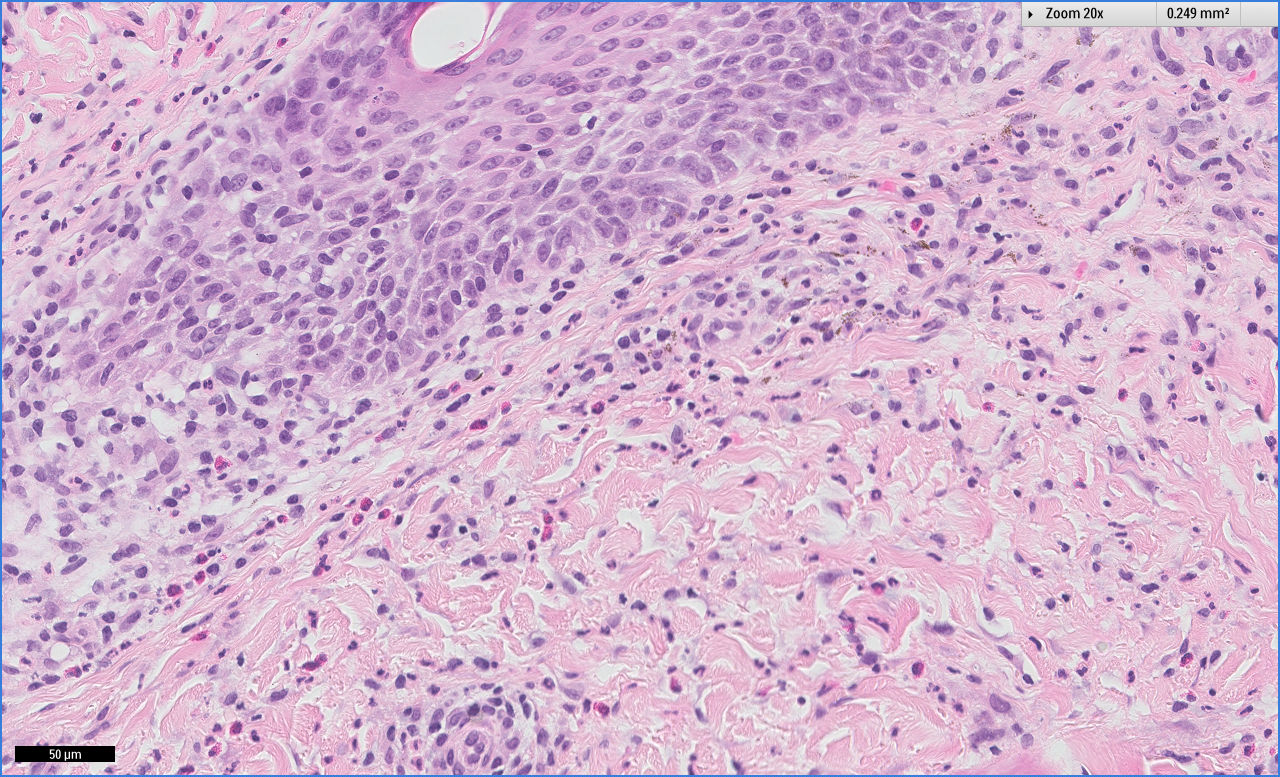

Case Presentation: The patient is a 29-year-old female with the history of acute pancreatitis and gastric bypass surgery, who initially presented with lower extremity swelling in the setting of hypoalbuminemia and protein-calorie malnutrition. She was started on high calorie/protein diet and was discharged on furosemide. Three weeks after discharge, she noticed peri-oral rash, which extended to lower extremities, groin, and trunk. On presentation, she had multiple areas of erythema and crusting over the body with small tense vesicles of legs and bilateral lower extremities edema. Blood work showed elevated liver enzymes, elevated INR, low vitamin D, normal hemoglobin and elevated eosinophils. She underwent left forearm skin biopsy, which showed findings consistent with drug hypersensitivity. She was diagnosed with DRESS syndrome and was started on Prednisone secondary to liver dysfunction. Her liver function improved and rash resolved. She was discharged on Prednisone for outpatient slow taper. She presented again with complaints of weakness, fatigue, and dyspnea on exertion. Completed blood count showed hemoglobin 8.5 gram/dl, which later dropped to 7.1 gram/dl. No source of bleeding was identified. Hemolysis work-up came back positive with elevated LDH, low haptoglobin, elevated reticulocyte count and positive Coombs test. She received IVIG therapy and continued with Prednisone. Her hemoglobin levels remained stable without any further drops. She completed outpatient Prednisone taper over 6 weeks and her hemoglobin normalized to 12.1g/dl on 6 months follow up, without any recurrence of hemolysis.